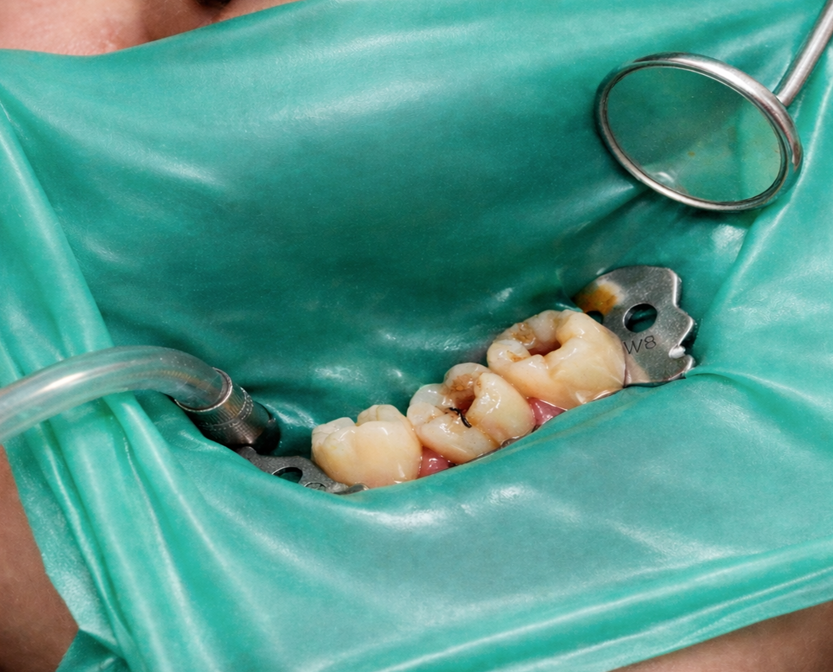

根管治療では、治療部位を汚染させないことが、その歯の予後(生存率)を大きく左右します。ラバーダムとは、治療する歯のみを露出させるための薄いシートで、唾液や歯周病菌・虫歯菌などが治療部位へ入り込むのを防ぐ目的で使用します。

根管内に細菌が侵入すると、治療の成功率は著しく低下します。そのため、不要な汚染を遮断できるラバーダムは、根管治療において欠かせない器具です。

また、視野が安定し、治療部位が明確になることで、より精度の高い丁寧な処置につながります。

④ ラバーダムをおこないます。

お口の中や唾液には細菌が多く存在するため、根管を無菌化することが目的の感染根管治療の際には、唾液などから隔離するためにラバーダムをおこないます。当院では原則ラバーダム防湿ができるすべての症例でラバーダムをおこなっています。